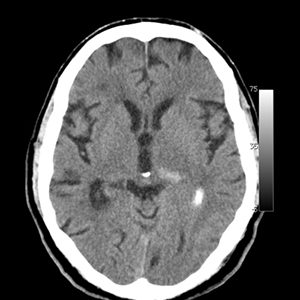

CT cerebral

Se pot determina leziuni traumatice, malformaţii, anevrisme, tromboză sau hemoragie, tumori, hidrocefalie, traumatisme ale feţei, afecţiuni ale osului temporal (ureche) sau ale sinusurilor.